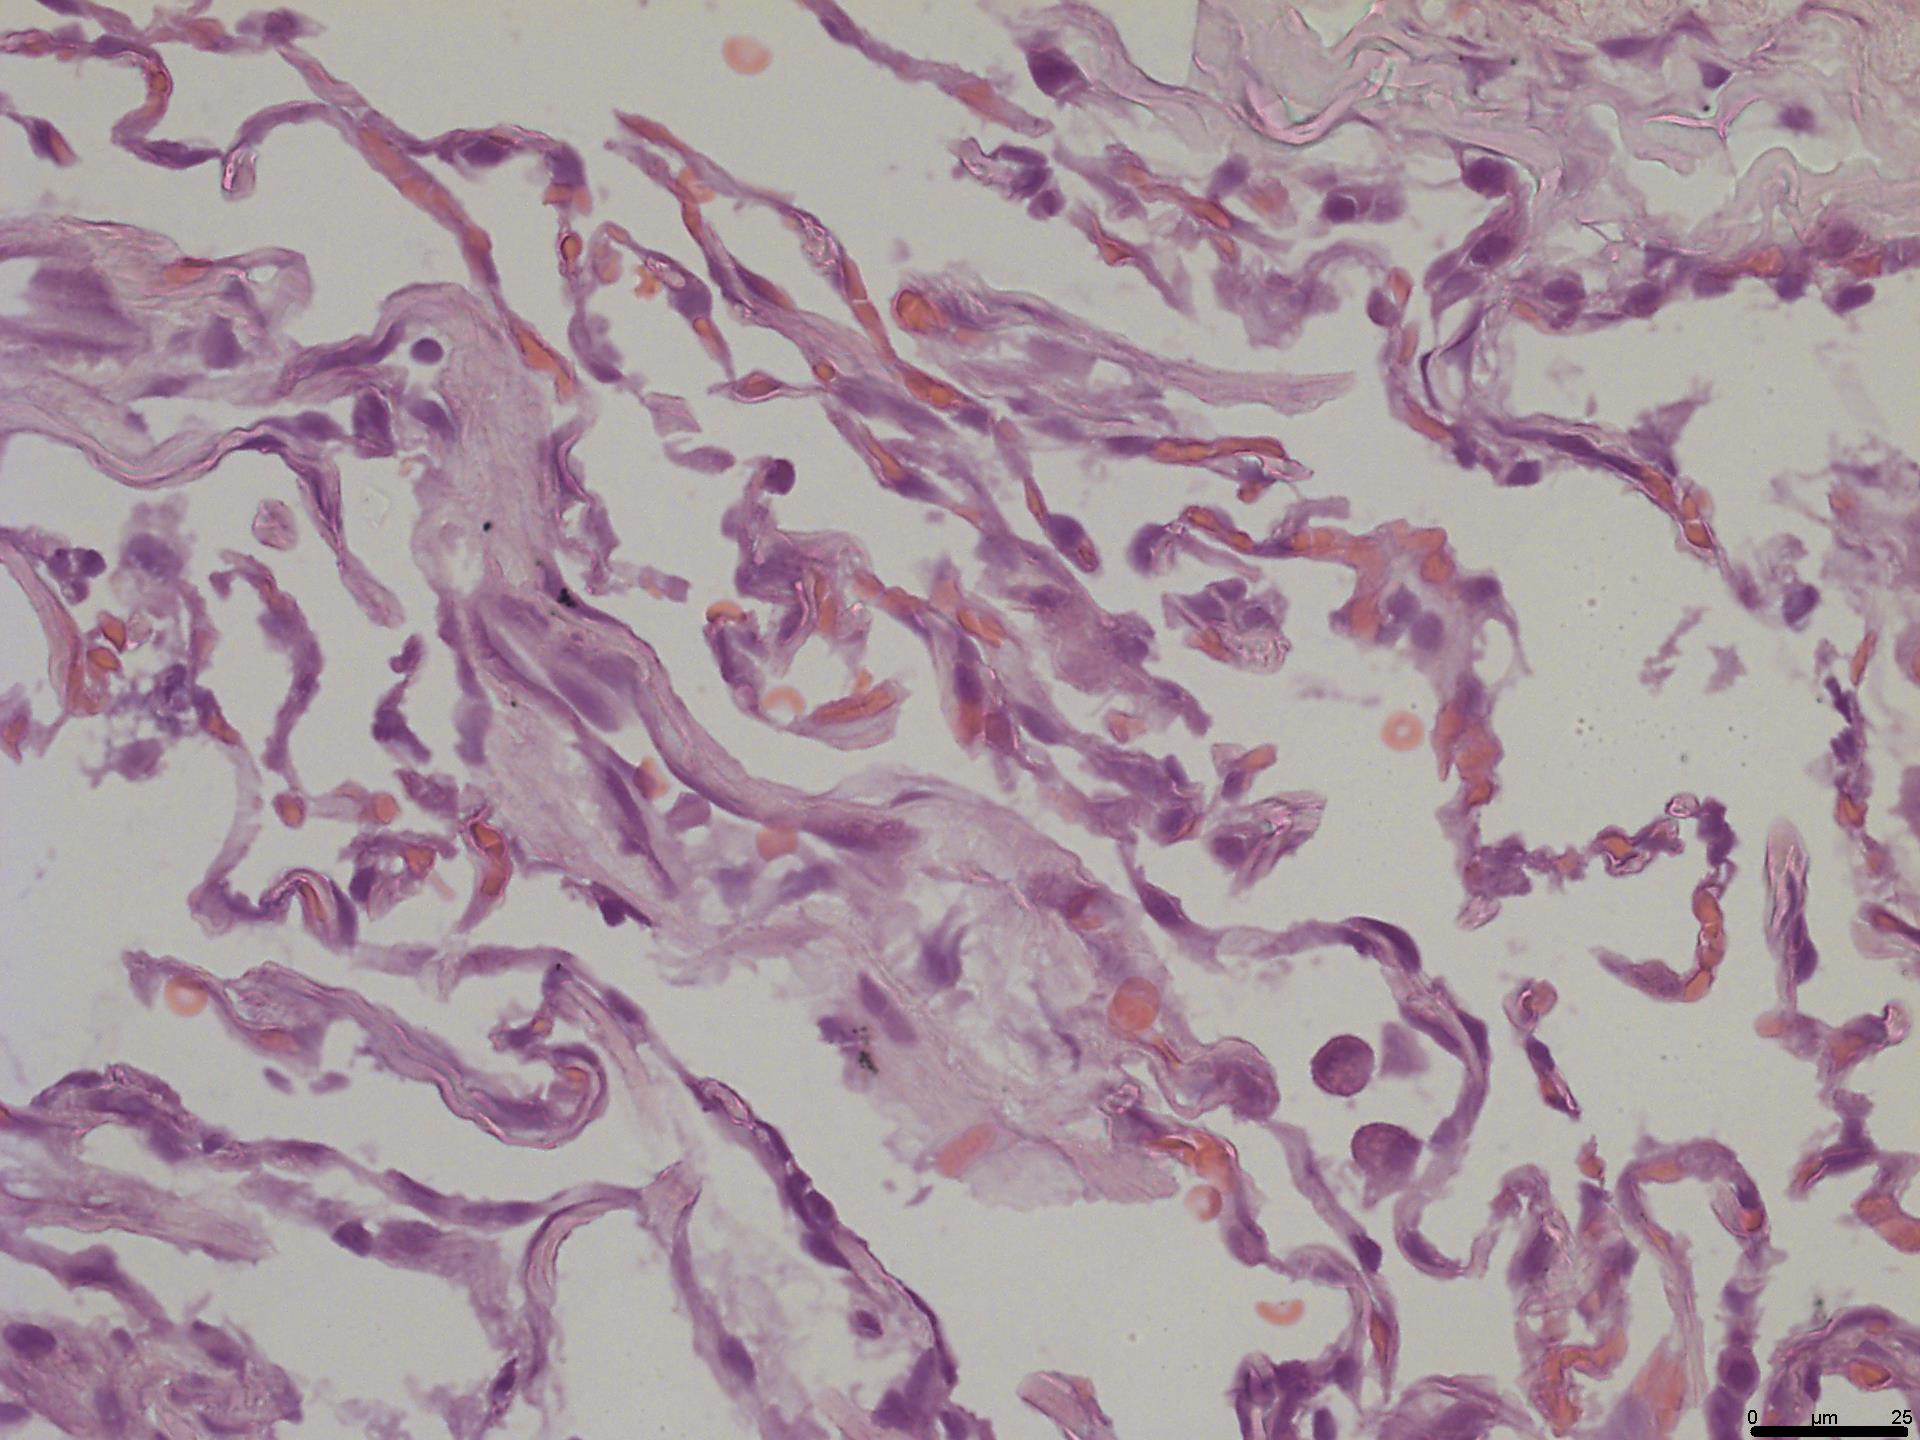

2. We suggest H&E staining as mandatory to validate the condition of the cultured explants at all time points. Specimens withdrawn at day 0 (step A6) must be processed to confirm that the tissue is initially intact (Figure 3). This is done by a pathologist.

10. IHC staining (slide 2): Use immunohistochemical (IHC) staining to reveal the antigens of interest. To confirm infection, we visualized the SARS-CoV-2 N protein by immunohistochemistry:

14. Image the sections using a light microscope with a digital camera (Figure 4).